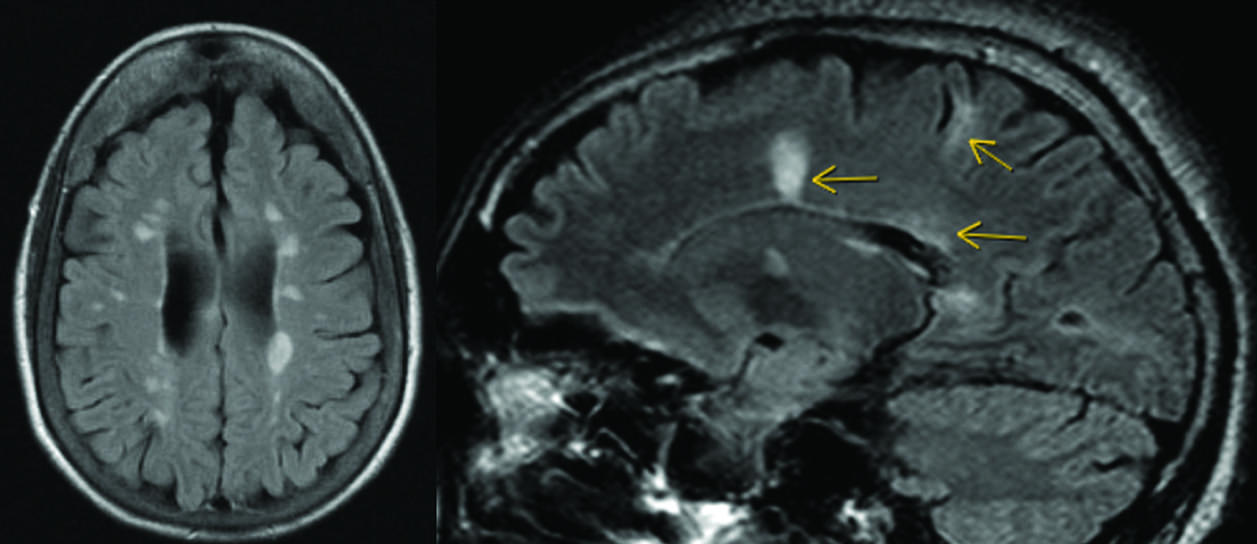

This randomized clinical trial indicates that a postpartum blood pressure management intervention after hypertensive disorders of pregnancy may be associated with favorable brain structure during the first year post partum. The intervention was linked to larger white matter volumes across women with hypertensive pregnancy (gestational hypertension and preeclampsia). In addition, women with a history of preeclampsia in the usual care arm showed smaller subcortical brain volumes at 6 to 9 months post partum than those with gestational hypertension; these differences were not evident among women in the intervention arm.

Both women with preeclampsia and gestational hypertension experience high blood pressure during pregnancy that frequently persists post partum.28 Lower white matter integrity has been reported from the peripartum period into later life.3,12,29 Hypertension-related white matter injury30,31 is associated with slower processing speed, executive dysfunction, and memory impairment.31 Although cognitive impact may not be obvious in the early postpartum period, white matter changes predict later cognitive decline and dementia,32 and converging longitudinal evidence suggests that reductions in white matter volume and integrity track cognitive decline, supporting the interpretation that better-preserved white matter is beneficial.33

Whether postpartum white matter changes are preventable or reversible had not been investigated. In this randomized clinical trial, a short-term blood pressure control intervention was associated with larger brain volumes several months later, when most participants were no longer taking antihypertensive medication. This is consistent with the postpartum period as a critical window for pregnancy-associated brain volume and blood pressure changes. Because baseline brain MRIs were not acquired, we cannot distinguish recovery of pregnancy-related changes from a slower postpregnancy decline relative to usual care.